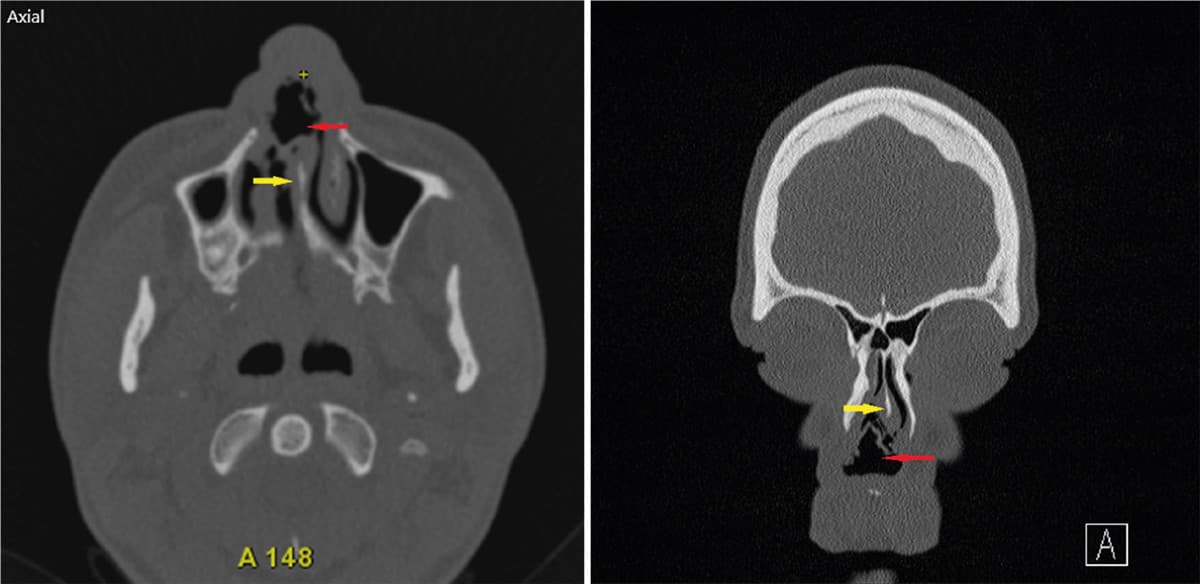

En patient i slut-20’erne har efter et flerårligt forbrug af intranasal kokain udviklet komplikationer i form af destruktion af columella og hele den bruskede del af septum. Dette har medført sammenfald af næsen. Patienten er generet af udtalt nasalstenose, skorpedannelse og gentagne infektioner med Staphylococcus aureus i det resterende væv i næsen. Der er i forløbet lavet en CT, som viser total borterosion af den bruskede del af septum. Det er ikke vurderet muligt at rekonstruere næsen kirurgisk, og patienten er henvist til vurdering i forhold til behandling med protese.

Kokain er en vasokonstriktor, som nedsætter blodgennemstrømningen i væv, og derved er der risiko for nekrose og vævsdestruktion. En kendt komplikation til kokainmisbrug er destruktion af den bruskede del af næseskillevæggen [1]. I nogle tilfælde ses der destruktion i en sådan grad, at både knogle og hud bliver påvirket. Der er i litteraturen også beskrevet tilfælde, hvor store dele af den hårde gane er destrueret [2, 3].